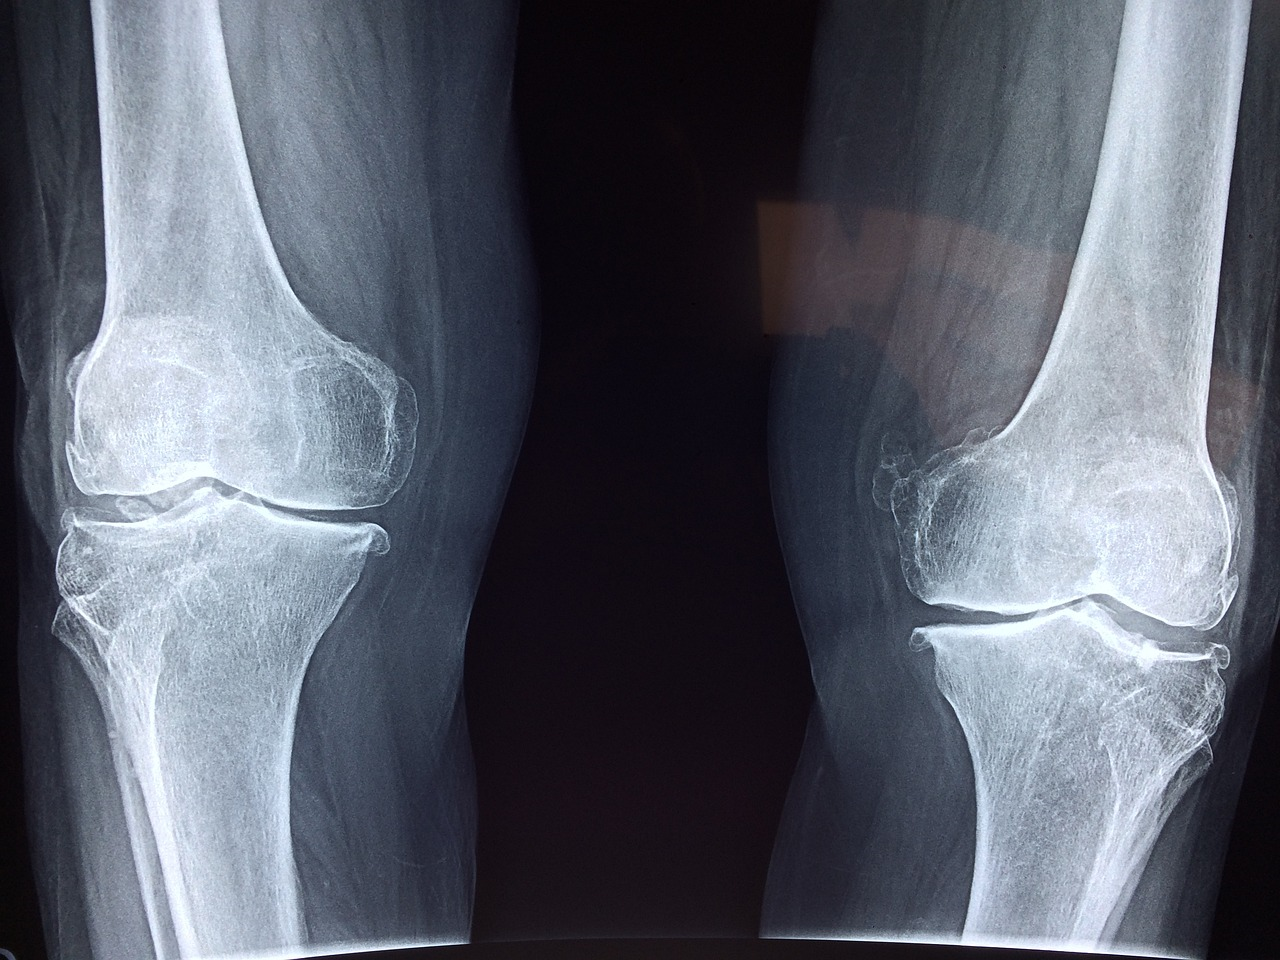

● 무릎안쪽 통증은 주로 관절염, 인대 손상, 골관절염 등 다양한 원인으로 발생합니다. 통증의 정도나 지속 시간에 따라 치료법이 달라지는데, 약물 치료와 물리치료, 수술 등이 있습니다.

● 관절염은 무릎 관절의 염증으로 통증, 부종, 강직감 등의 증상을 유발하며.

● 골관절염은 뼈와 뼈 사이의 연골이 닳아 통증을 유발합니다.